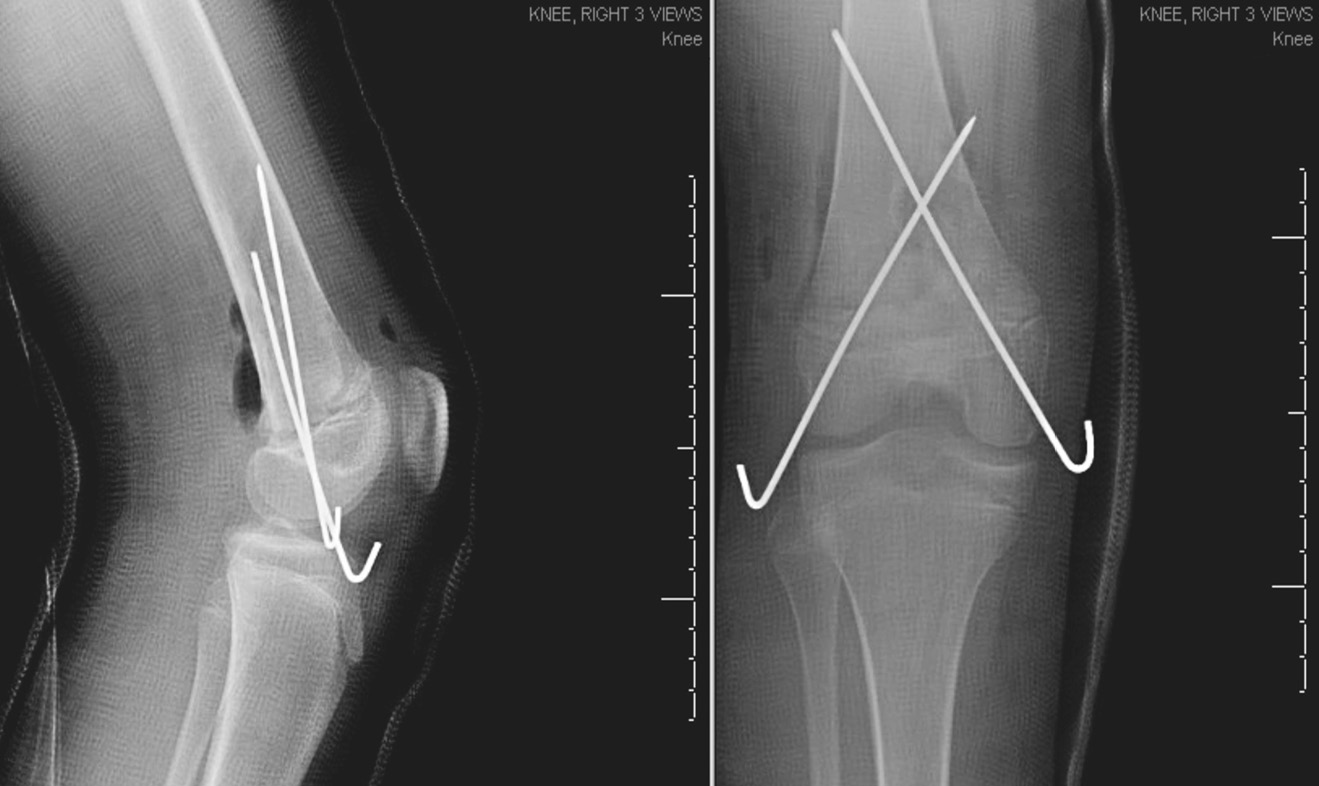

Был выполнен заднебоковой разрез в области дистального отдела правого бедра. После тщательного промывания 9 л изотонического раствора натрия хлорида была высвобождена ущемленная надкостница и выполнена репозиция перелома. Перелом зафиксирован в удовлетворительном положении с помощью перекрестной установки спиц через дистальный эпифиз бедренной кости. Нормальное кровоснабжение было подтверждено допплерографически, и рана ушита. Пациентке был наложен длинный гипс без возможности опоры на ногу. На послеоперационных рентгеновских снимках видна удовлетворительная репозиция дистальной части бедра (рис. 3). Поскольку пациентка была иногородней и ее дом находился в 3 часах езды от больницы, врачи рекомендовали ей остаться в больнице на 2 дня во избежание развития компартмент-синдрома или нейрососудистых нарушений и для завершения 48-часового введения цефазолина внутривенно. Затем пациентка была выписана домой. Девочка оставалась в гипсе без опоры на ногу в течение 4 нед. Спицы были удалены через 6 нед. По истечении 6 мес. пациентка прошла контрольное обследование, которое показало, что она не испытывает затруднений в движении. Восстановление прошло успешно, и ребенок снова смог посещать уроки физкультуры. На заключительных рентгенологических снимках через 6 мес. репозиция сохранялась. Пациентка наблюдалась в течение 2 лет, при этом у нее не было отмечено угловой деформации конечности или различия в длине ног.

Рис. 3. Рентгенограмма правого коленного сустава в переднезадней и боковой проекциях после открытой репозиции и внутренней фиксации. Видна нормальная репозиция с фиксацией двумя спицами, перекрестно установленными через эпифиз